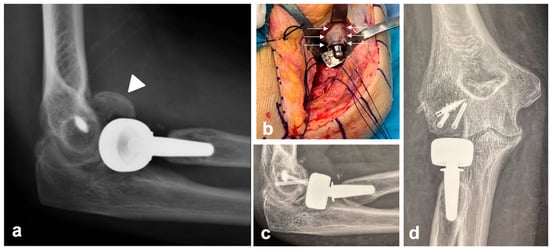

No implant-related complications were detected at the last radiographic evaluation. No patients underwent reintervention during the follow-up owing to stem failure-related complications. Three patients suffered a disassembly of a bipolar prosthesis 4, 5, and 10 years after the index procedure following a new trauma. In the first patient, the radial head component was replaced and the LCL was reconstructed. In the second and third patients, the disassembly was associated with capitellar fracture; these two cases both underwent osteosynthesis with two headless screws and replacement of the radial head component. The mPRNR was moderate in one of these three patients, severe in another, and moderate in the last. The stem appeared to be well integrated in all three cases, with no need for revision (Figure 5).

Figure 5.

Clinical case of a patient who experienced disassembly of a bipolar prosthesis 10 years after the index procedure following a new trauma. The disassembly was associated with a capitellum fracture (white arrowhead) (a); the mPRNR in this patient was moderate. The stem appeared to be well integrated, with no need for stem revision (b). The intraoperative appearance of PRNR is also shown in (b) (white arrows). Osteosynthesis with two headless screws and replacement of the radial head component were performed (c,d).